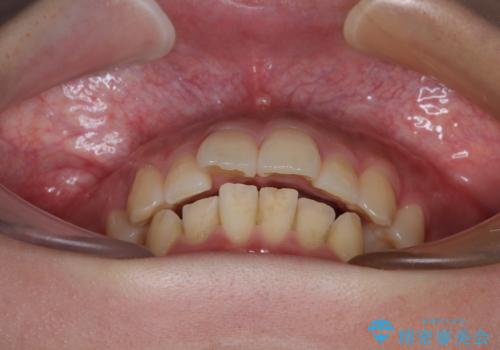

- 前歯のデコボコと口元の突出感を気にして来院された患者様です。

上下前歯がくちばしのように突出していたため、上下左右の第一小臼歯4本を抜歯し、ワイヤー装置にて矯正治療を行うこととしました。

口元の突出感が改善されてことで、下唇に引っかかっていた上顎前歯も気にならなくなりました。